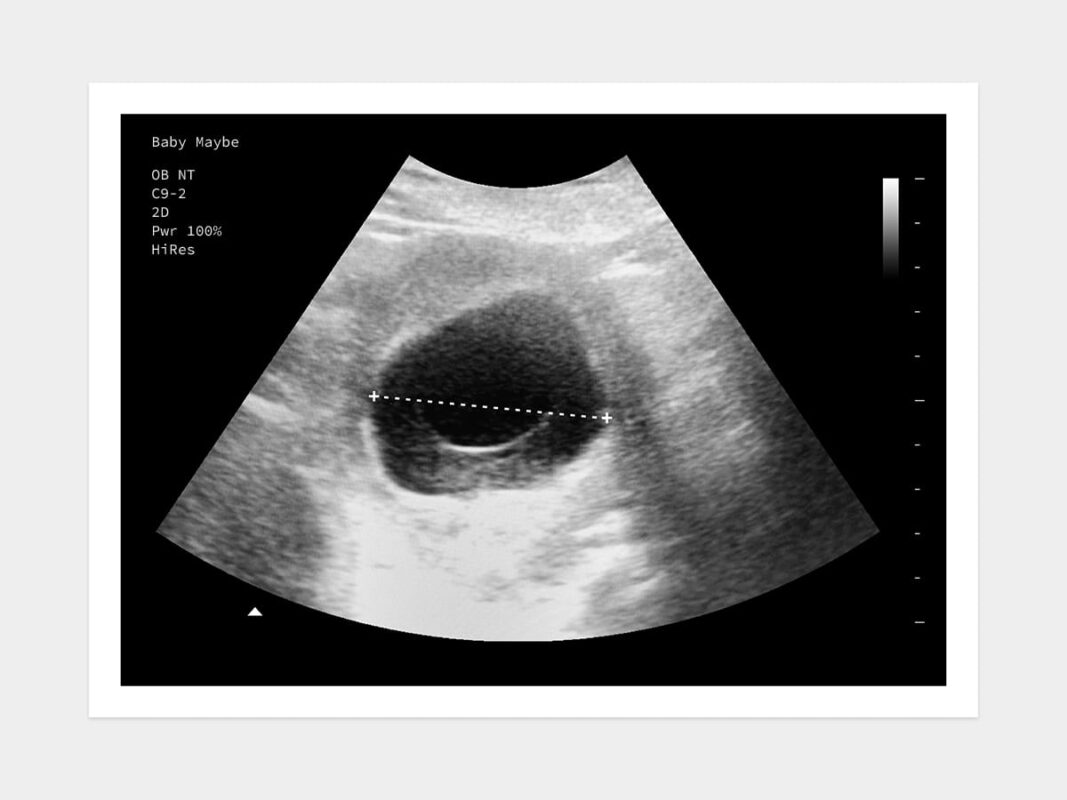

Siêu âm lặp lại sau 7-14 ngày

sieu am thai 1

Ảnh trên: Siêu âm

Đây là chỉ định bắt buộc và quan trọng nhất. Bác sĩ sẽ hẹn tái khám để siêu âm lại sau khoảng 1 đến 2 tuần.

Khoảng thời gian này đủ để thai kỳ phát triển (nếu là thai bình thường) đến mức có thể quan sát rõ ràng phôi thai và tim thai. Tại lần siêu âm sau, bác sĩ sẽ đánh giá sự thay đổi kích thước của túi thai và sự xuất hiện của phôi/tim thai.

Về hình ảnh siêu âm

– Thai 5 tuần (chưa thấy phôi): Siêu âm chỉ ghi nhận túi ối, có thể kèm túi noãn hoàng.

– Thai 5 tuần (đã thấy phôi): Nếu tuổi thai chính xác là 5 tuần 3-5 ngày, bác sĩ có thể thấy một cấu trúc phôi nhỏ (embryo pole) nằm cạnh túi noãn hoàng. Tim thai cũng có thể bắt đầu xuất hiện dưới dạng nhấp nháy từ cuối tuần thứ 5 hoặc đầu tuần thứ 6.